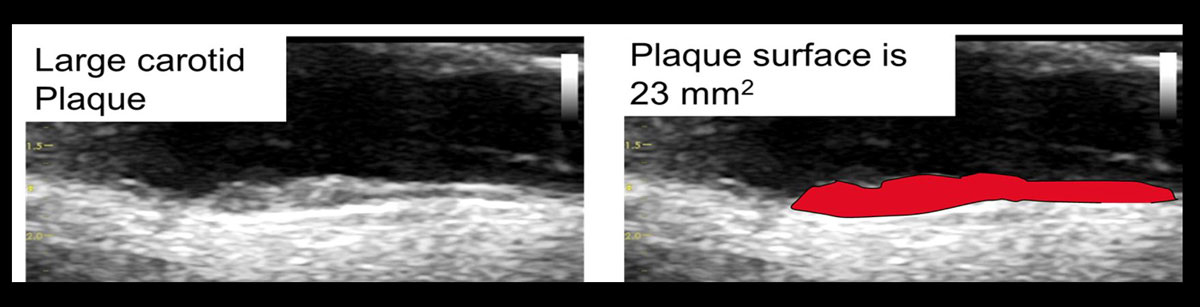

Given the excellent predictive accuracy for cardiovascular events of carotid TPV, which is indeed comparable to presence [65] and extent of coronary calcifications [34], it might be argued that carotid TPV should be used instead of carotid TPA. The correlation between carotid TPV and TPA was tested by the core laboratory in Ontario, Canada, which showed an extremely good correlation: r2 = 0.921 (p <0.0001) [19]. TPA has been shown to change by about 10 mm2 per year, which makes it suitable for observing therapeutic effects over time [20, 71]. In order to avoid the problem of missed plaques situated in the lateral wall with TPA, plaque area may be measured from transverse images (fig. 6).

Figure 6 Large carotid plaque in the carotid bulb, which contains plaque formation not visible in the longitudinal image.

Figure 7 Clinical significance of plaque measurements by integration of the Bayes theorem. A plaque area of 23 mm2 (see fig. 6) corresponds to an arterial age of 34 years in men and 43 years in women. An arterial age of 70 years corresponds to a total plaque area (TPA) of 108 mm2 in men and 66 mm2 in women, with increased risk [112]. On the basis of data from the Tromsø study, an arterial age of 70 years corresponds to the 96th percentile in men (sensitivity 9%, specificity 97%) and to the 95th percentile in women (sensitivity 18%, specificity 95%). According to the Bayes theorem, a person with a 4% risk and arterial age of 70 would then be reclassified to intermediate risk (men 11%, women 13%). For a 10-year risk of 10%, an arterial age of 70 would increase the risk to 25% in men and 29% in women.